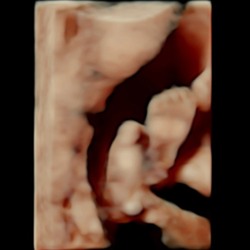

Wat denken jullie ?? 13 weken

Meisje!

🩷